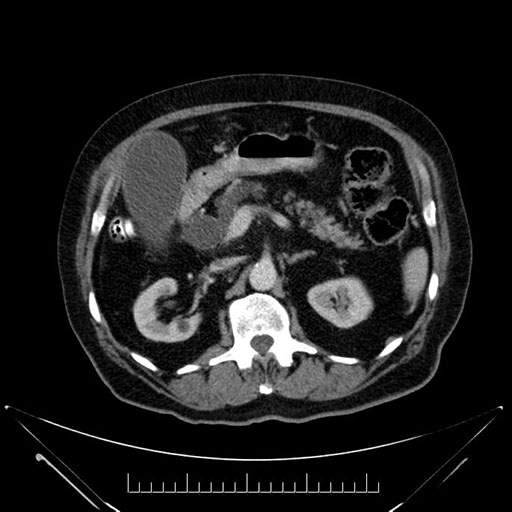

Axial - stented